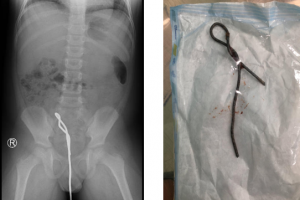

Tuần qua bệnh viện Nhi đồng Thành phố tiếp nhận trẻ N.V.S. 8 tuổi, nam, cân nặng 26 kg, ngụ ở quận Bình Chánh, Tp.HCM trong tình trạng sốt cao đau bụng. Khai...